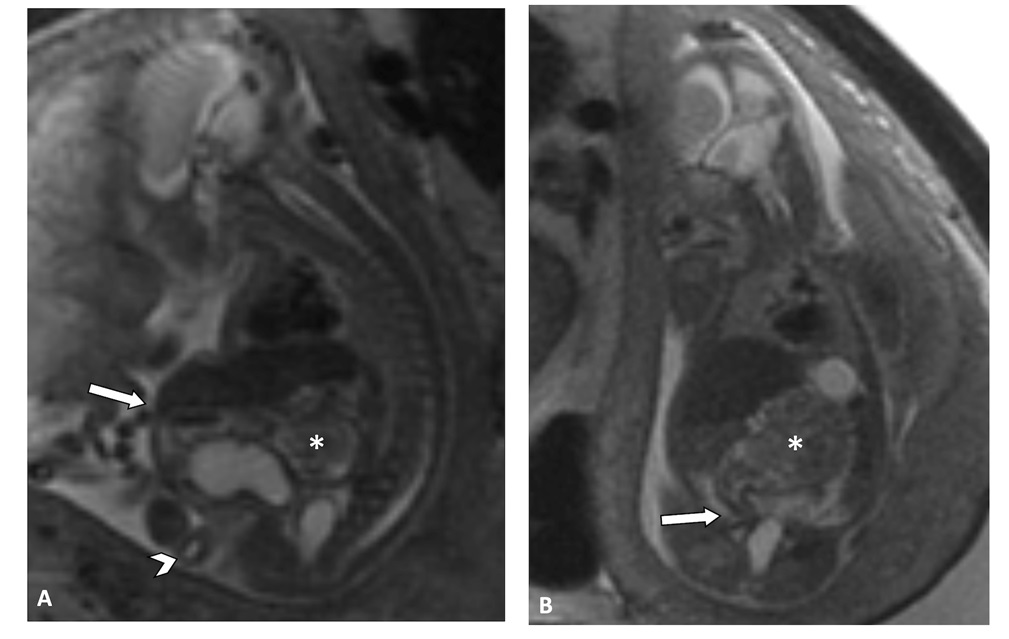

Figure 1: Congenital pouch colon, megalourethra, and prune belly syndrome on fetal MRI (3T) in a 30-year-old woman at 20 weeks 1 day. A) Sagittal T2WI shows the protuberant abdomen characteristic of prune belly syndrome, dilated and fluid-filled penile urethra (arrowhead), and pouch colon (*). B) Coronal T2WI shows abrupt tapering of the pouch colon (*) at the level of the rectosigmoid junction (arrow). The patient was induced at 36 weeks and 5 days for fetal growth restriction and delivered vaginally without complication.